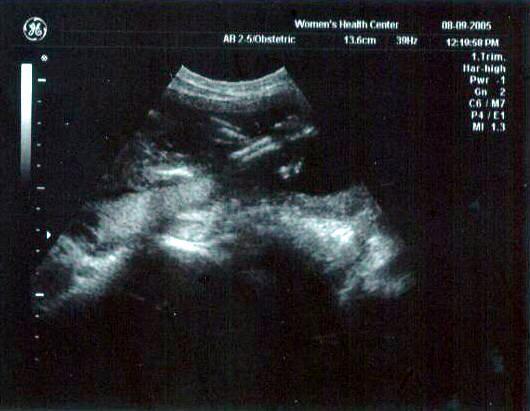

13 week ultrasound ~ The little one's getting bigger!